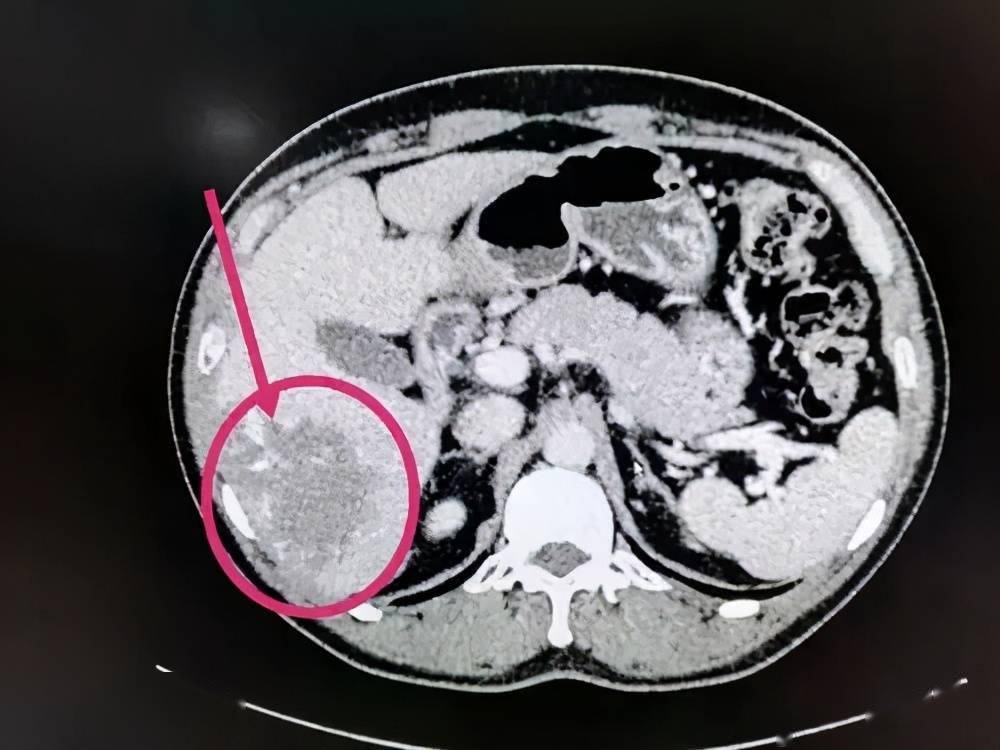

呼和浩特市第一医院医学影像科黄色肉芽肿性胆囊炎病例解析

图片尺寸469x590